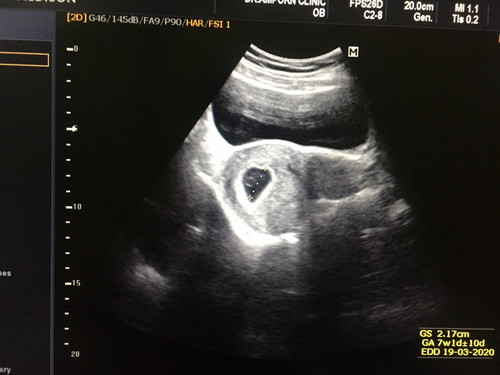

ซาวท้องตอน 8w6d คุณหมอบอกว่า เด็กตัวเล็กมาก

วันนี้ซาวน้องตอน8w6dเห็นแต่ถุงการตั้งครรภ์ กับถุงไข่แดง เห็นเงาเด็กจางๆ คุณหมอบอกไม่แฮปปี้ ระหว่างนี้ถ้ามีเลือดออกไม่ต้องกังวล เครียดมากเลย ท้องแรกด้วยค่ะ

เป็นไปได้ว่าไข่อาจจะตกช้า การนับอายุครรภ์อาจจะคาดเคลื่อน ความจริงน้องอาจจะยังตัวเล็กอยู่ค่ะ แนะนำให้รออีก 2 อาทิตย์แล้วไปซาวด์ใหม่นะคะ